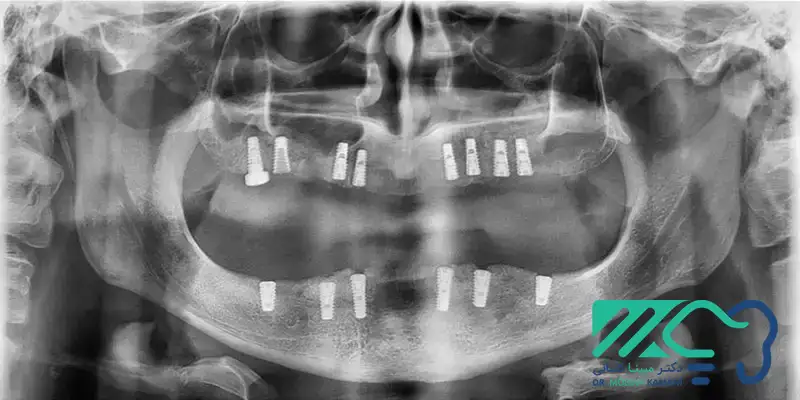

نمونه کار ایمپلنت دندان+عکس بعد از جراحی ایمپلنت

یا به دنبال راهی برای جایگزینی دندانهای از دست رفته خود هستید؟ ایمپلنت دندان یکی از بهترین و پایدارترین روشها برای بازگرداندن لبخند زیبا و عملکرد کامل دهان است. با کاشت ایمپلنت، میتوانید از دندانهایی قوی و طبیعی برخوردار شوید که سالها برای شما ماندگار خواهند بود. نمونه کار ایمپلنت دندان میتواند دید بهتر و […]